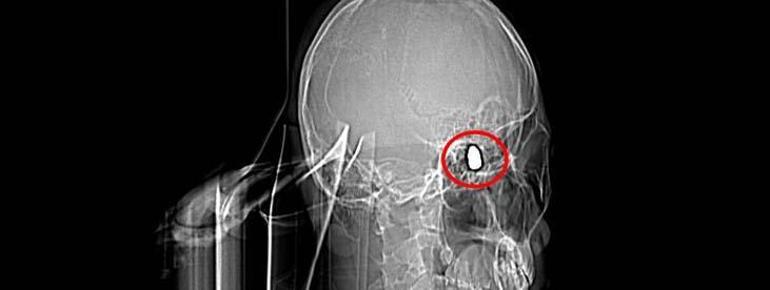

Olay, 5 Kasım 2023’te Bahçelievler Mahallesi 1624’üncü Sokak’ta meydana geldi. Arkadaşları ve ağabeyiyle maça gitmek için konutundan çıkan Yusuf Emre Özbek, birlikte fotoğraf çektirdikten çabucak sonra yere yığıldı. Etraftakilerin hastaneye götürdüğü Yusuf’un çekilen röntgeninde, başında mermi çekirdeği olduğu tespit edildi.

4 gün ağır bakım, 4 gün de serviste tedavi gören Yusuf’un başındaki mermi için hekimler, riskli bölgede olduğu gerekçesiyle müdahale etmedi. Tertipli olarak denetim edilen Yusuf’ta konuşma zahmeti ve sağ el ve parmaklarında zayıflık belirtileri ortaya çıkınca, fizik tedavi süreci başladı.